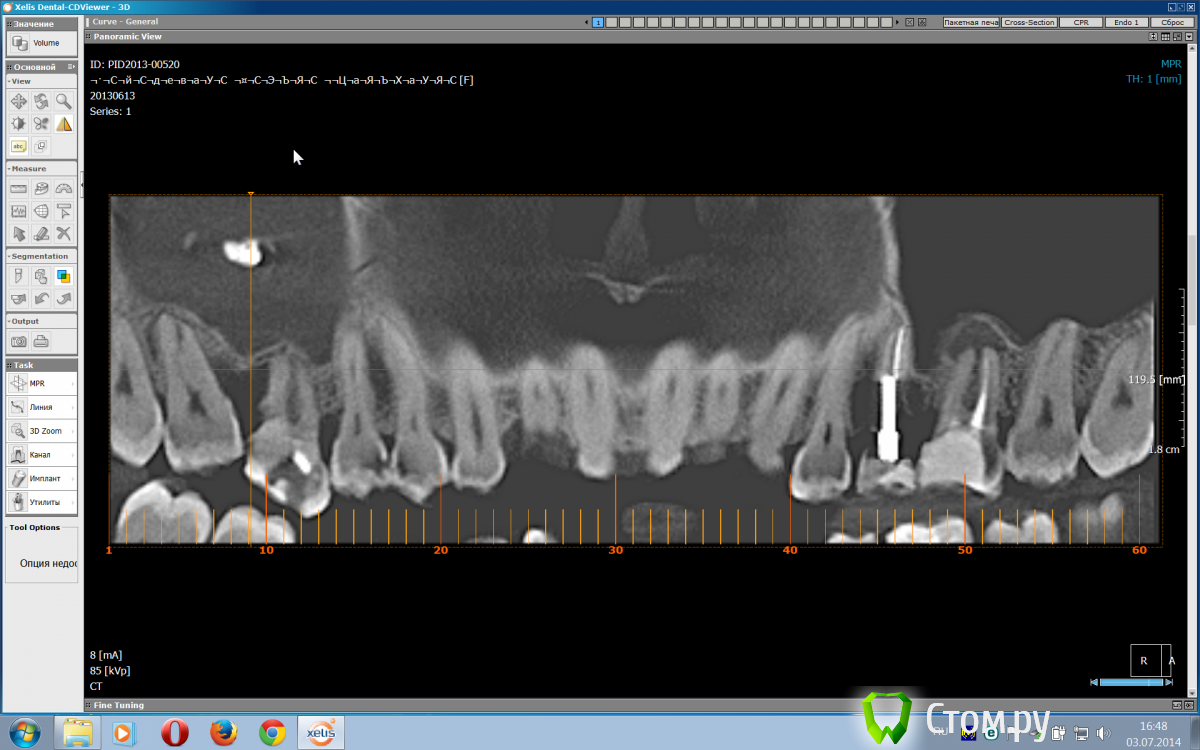

TIGER Опубликовано 4 июля, 2014 Поделиться Опубликовано 4 июля, 2014 Пациентке необходимо провести синус_лифтинг,но на КТ такая картина(Наши ЛОРы предлагают через латеральный доступ санировать,но я переживаю,что они там распотрошат всю пазуху.Как быть?!Причинный зуб 16 удалил уже.http://s018.radikal.ru/i526/1407/1b/7ba0b01493e5.png Ссылка на комментарий

kriokov Опубликовано 4 июля, 2014 Поделиться Опубликовано 4 июля, 2014 мне кажется, как раз тот случай, когда надо ЛОР эндоскопически решать с инородным телом (FESS), о чем ILGAMSA в одной из тем пояснял. И показалось по кт, что остиум закрыт, хотя на коронарном срезе не все видно 3 Ссылка на комментарий

TIGER Опубликовано 4 июля, 2014 Автор Поделиться Опубликовано 4 июля, 2014 мне кажется, как раз тот случай, когда надо ЛОР эндоскопически решать с инородным телом (FESS), о чем ILGAMSA в одной из тем пояснял. И показалось по кт, что остиум закрыт, хотя на коронарном срезе не все видноНаши ЛОРы предлагают только радикальную гайморотомию...поэтому переживаю Ссылка на комментарий

Чертков Александр Опубликовано 5 июля, 2014 Поделиться Опубликовано 5 июля, 2014 Александр т.е реално самому через латеральный доступ санировать?Вполне. Сам ещё такие вещи не делал (только планирую ). Буквально на днях присутствовал у коллеги на операции (мой пациент). Ситуация один в один с Вашей. Я сначала тоже ЛОРа предлагал, но когда увидел - как это делается, то понял что не всегда надо к ЛОРам "гонять". Ключевой момент, который неоднократно напоминал Олег Юрьевич (Bier), это состояние соустья. Если там всё в норме, то можно самостоятельно решать подобные проблемы. Если сомневаетесь - то обязательно через ЛОРов. 2 Ссылка на комментарий

TIGER Опубликовано 5 июля, 2014 Автор Поделиться Опубликовано 5 июля, 2014 Вполне. Сам ещё такие вещи не делал (только планирую ). Буквально на днях присутствовал у коллеги на операции (мой пациент). Ситуация один в один с Вашей. Я сначала тоже ЛОРа предлагал, но когда увидел - как это делается, то понял что не всегда надо к ЛОРам "гонять". Ключевой момент, который неоднократно напоминал Олег Юрьевич (Bier), это состояние соустья. Если там всё в норме, то можно самостоятельно решать подобные проблемы. Если сомневаетесь - то обязательно через ЛОРов. Сомневаюсь,что там в норме.... Ссылка на комментарий

IvanK Опубликовано 5 июля, 2014 Поделиться Опубликовано 5 июля, 2014 Ключевой момент, который неоднократно напоминал Олег Юрьевич (Bier), это состояние соустья. Ссылка на комментарий